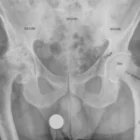

Standing X-rays are often sufficient for diagnosis:

- Measure the alignment of the bones in the toes.

- Evaluate damage to the metatarsophalangeal joint. Long-standing hallux valgus can be accompanied by arthritic changes.